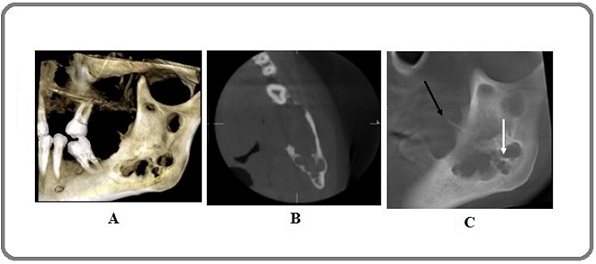

After a complete extraoral and intraoral examination, considering the centrality of the lesion and the unexplained increase in size, as well as the prevalence and location of the lesion, the possibility of an odontogenic tumor with malignant transformation was initially raised. Panoramic radiography showed a multilocular radiolucent lesion extending from the distal region of the left mandibular second molar to the neck of the condyle and below the sigmoid notch. A bony projection resembling a periosteal reaction was seen at the anterior border of the ramus (Figure 2).

Figure 2. Panoramic View: General view of the lesion on the left side of the mandible with extension towards the ramus (in the panoramic radiograph of the patient, a multilocular lesion is seen in the posterior region of the mandible from the distal second molar to below the sigmoid notch)..

CBCT showed erosion and perforation of the buccal and lingual walls, as well as a downward displacement of the inferior alveolar nerve canal and anterior tilt of the left mandibular second molar. Sagittal planes showed a large lacuna that perforated the anterior ramus wall, and the remaining walls appeared similar to the periosteal reaction (Figure 3).

Figure 3. A, CBCT (3D view): multilocular lesion and bony projections in the anterior wall of the ramus; B, CBCT ( Axial view): multilocular lesion (multilocular with coarse septa); C, CBCT (sagittal view): The lesion is multilocular with coarse septa (white arrow). Note the bony projection (black arrow) that closely resembles a periosteal reaction.